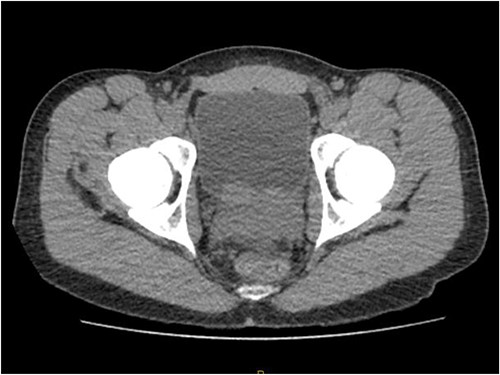

Laboratory tests of full blood count and liver function test were unremarkable with prostate specific antigen of 0.53. Mid-stream urine MCS did not show any infection and urine cytology was negative. Renal function test revealed progressive worsening of previously normal eGFR down to 27 ml/min. Initial renal tract ultrasound (Fig. 1) showed enlarged prostate indenting into the bladder base with high post micturition urine residual volume of 185 ml but no hydronephrosis. CT KUB (Fig. 2) showed irregularly enlarged prostate with bilateral hydroureteronephrosis. MRI prostate showed enlarged prostate with PIRADS 5 amorphous mass suspicious for carcinoma involving bilateral seminal vesicles and right vesicouretric bladder. FDG PET (Fig. 3) showed unusual distribution pattern of lymphoma involving the prostate with bilateral symmetrical renal, early pulmonary, and possibly right thyroid lobe involvement.